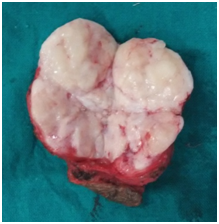

The patient was operated under general anaesthesia. Incision was given in skin and subcutaneous tissue. On undermining both flaps a solid mass started protruding from the incision (Figure 2). The size of this lump was 11cmx10cm (Figure 3). Haemostasis was achieved using electrocautery. The excised specimen had a well defined capsule similar to fibroadenoma of breast (Figure 4). The cut surface of specimen had a whitish lobular appearance (Figure 5). The histopthological diagnosis was confirmed as fibroadenoma. Microphotographs show intracanalicular type of fibroadenoma having plenty of stroma (Figure 6). The postoperative period was uneventful and stitch line was healthy after stitch removal.

Figure 5 Specimen Cut Transversely.

Figure 6 Microphotograph showing Intracanalicular Fibroadenoma